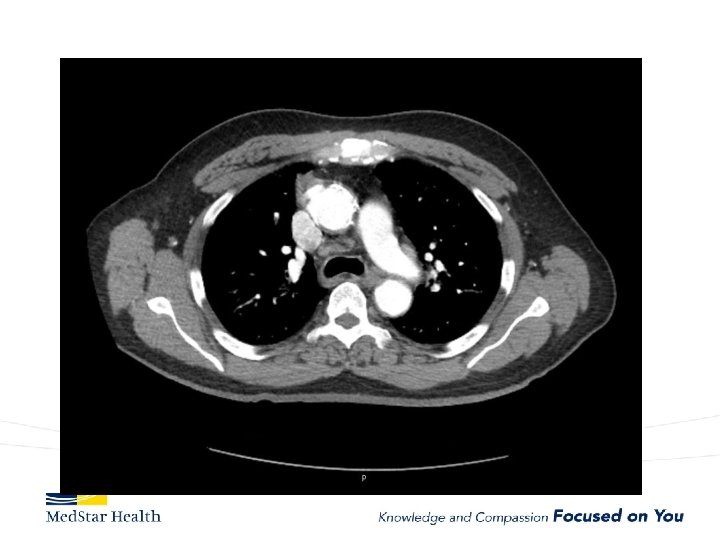

Acute Type B Aortic Dissection • Incidence: 2. 6 -3. 5 per 100, 000 patient-year • Uncomplicated • Complicated – – Malperfusion Rupture Unremitting Pain Uncontrolled HTN

Type B Dissection Complicated Uncomplicated Risk TEVAR age, comorbidities Extreme Low Medical Management False Lumen Small, Thrombosed Medical Management Patent/Large(>22 mm), Total Aorta >40 mm TEVAR/adjuncts